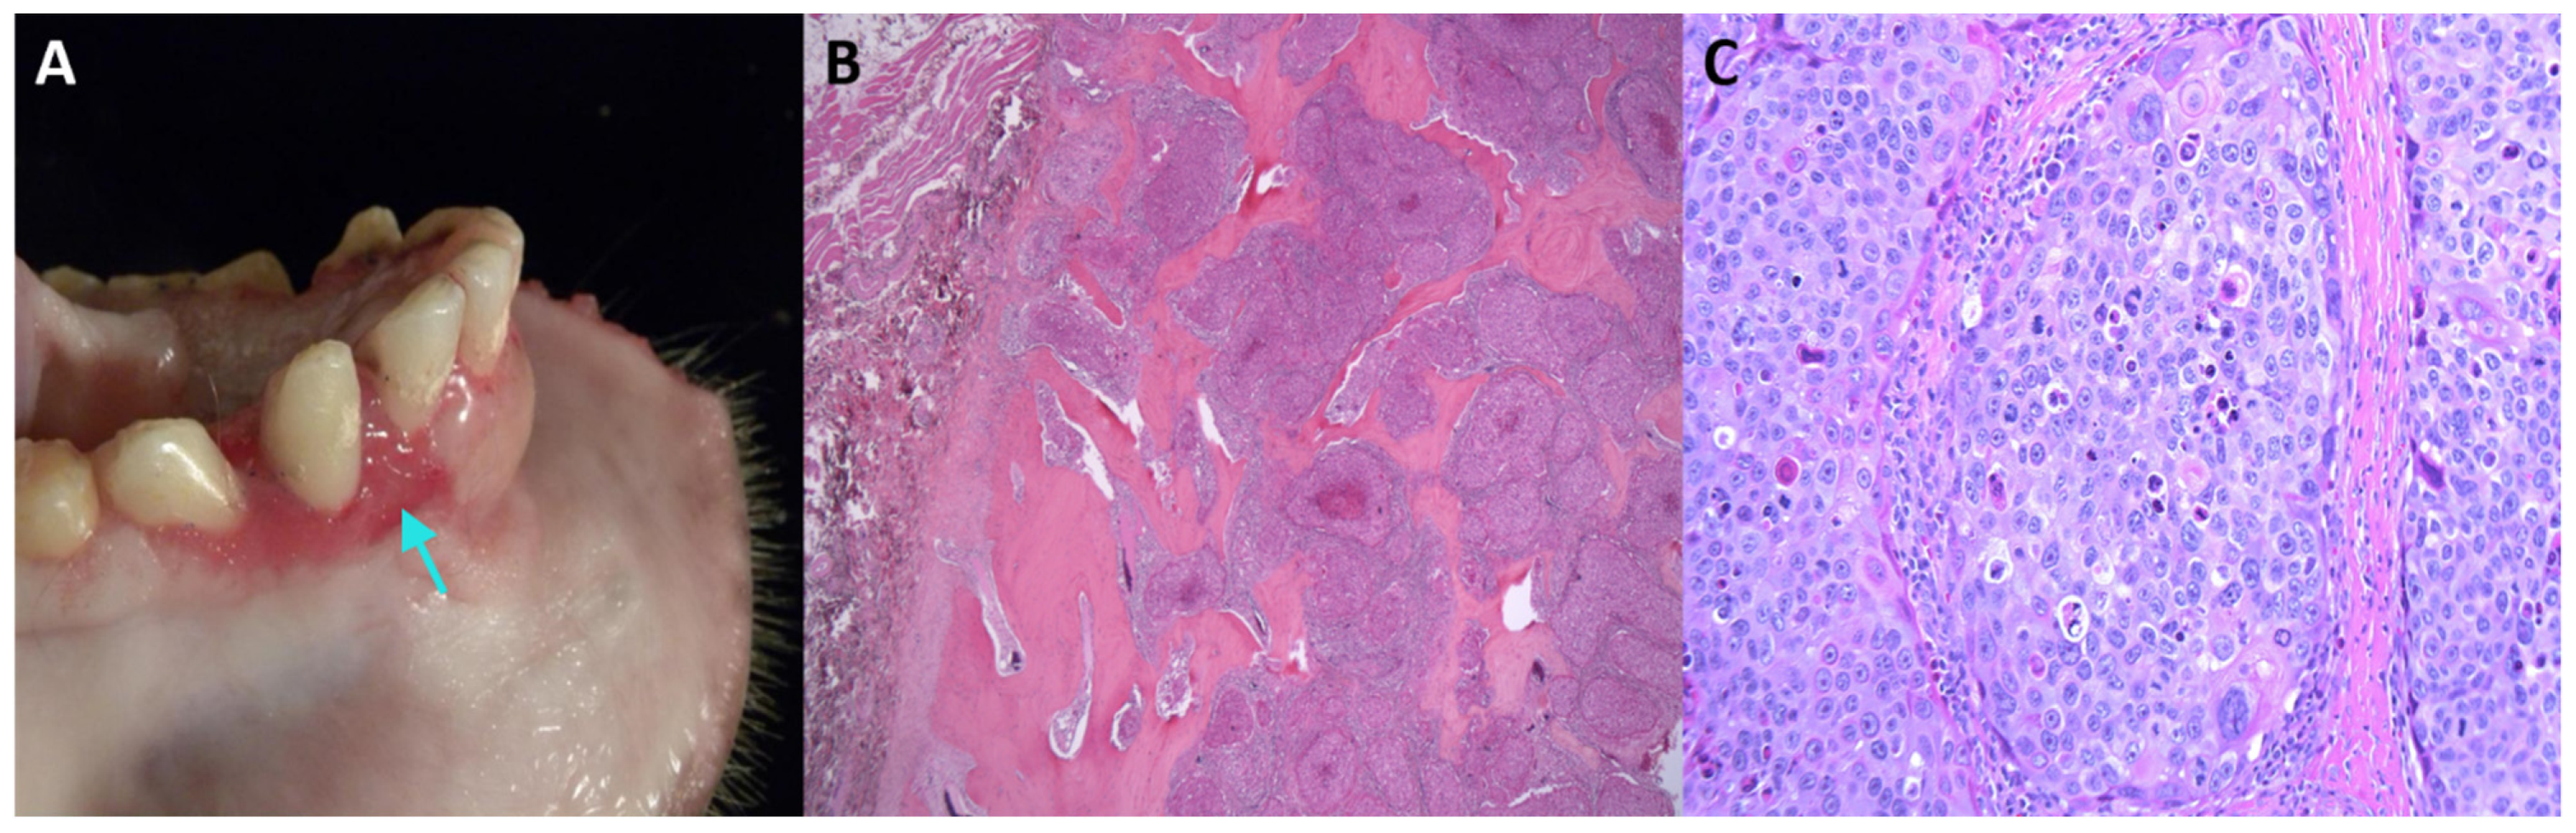

We detected MfuPV1 in an oral lesion of a 14-year-old female Japanese macaque (Figure 1). Specifically, the mentioned lesion was present as a fleshy, pink, soft tissue mass associated with the buccal gingiva of the mandibular incisors and extended into the buccal mucosa, lingual gingiva, and base of the frenulum. Histopathological analysis showed that the oral mucosa was ulcerated, and the submucosa was expanded by a poorly demarcated, densely cellular, endophytic and exophytic population of neoplastic epithelial cells arranged in nests on a densely collagenous to scirrhous stroma. Similar nests of neoplastic cells infiltrated and effaced the mandibular symphysis cortical and trabecular bone. Rafts of neoplastic cells were present within the lumen of salivary gland ducts in one section of the lingual mucosal surface and within the subcapsular sinuses of both submandibular lymph nodes. Finally, in the described tissue, pathologic findings confirmed the presence of a locally aggressive oral squamous cell carcinoma with mandibular invasion and submandibular lymph node metastasis (Table 1).

Figure 1. Oral squamous cell carcinoma in an adult female Japanese macaque. (A) Gross pathology of the oral lesion with a focus of gingival elevation and erosion on the rostral mandible (indicated by arrow). (B) Histopathological section showing a multilobulated, infiltrative neoplastic mass invading and effacing the mandibular bone (stained with hematoxylin and eosin, 20× magnification). (C) Higher magnification of (B) showing neoplastic cells arranged in islands (200× magnification). Neoplastic cells are polygonal, with distinct cell borders, a moderate amount of eosinophilic cytoplasm, large central nuclei with marked karyomegaly, multifocal multinucleated cells, and prominent nucleoli. Scattered individual neoplastic cells are shrunken and necrotic.